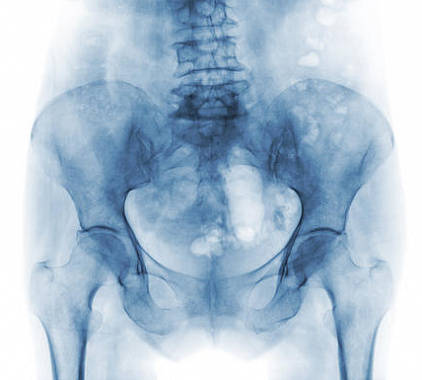

Полученные изображения рентгенолог анализирует сразу после рентгенографии. В описании он указывает состояние и структуру костей, крестцово-копчикового сустава, межпозвоночных дисков, позвонков, окружающих тканей. Доктор подробно описывает обнаруженные патологии и их параметры.

Посредством рентгена копчика становится возможным выявить травматические повреждения (вывих, перелом, ушиб), дегенеративно-дистрофические заболевания, деформации копчика, остеопороз, патологические процессы крестцово-копчикового сустава, гематому. Процедура информативна в плане визуализации остеохондроза, метастаз, аномалий развития, остеомиелита, новообразований злокачественного или доброкачественного генеза, воспалений, искривлений позвоночного столба.